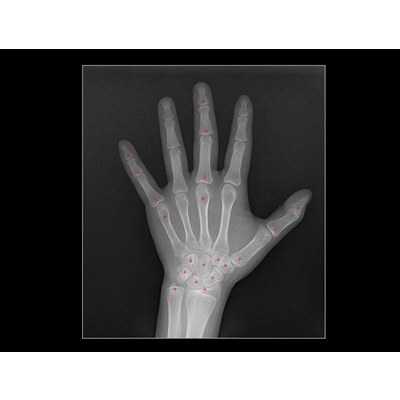

联影智能DR儿童生长发育智能分析系统可根据图谱法、TW3法、中华05法和TW3C法4种骨龄标准计算儿童骨龄,能够有效减轻医生工作量,大幅提升判读速度、稳定性和一致性。同时,可结合多项儿童生理生化指标,评估儿童生长发育状况,自动生成多维度图文报告,有效辅助儿童生长发育状态的诊断。

传统人工骨龄检测评估方式通常使用两种方式,图谱法和计分法。图谱法是与标准骨龄图谱直接对比,虽然评估速度快但一致性较差;而计分法则是分别评估掌指尺桡骨、 腕骨骨群的发育等级,得到骨龄结果,包括TW3法、中华05法等。骨化中心等级的细分可以减少主观判读,虽然评估准确但计算过程耗时耗力。

联影智能DR儿童生长发育智能分析系统支持多种骨龄评估标准,可针对特定区域医院,根据医院需求配置一种或多种骨龄评估标准。并且可对儿童的身高、体重等生长发育状况进行自动评估分析。基于uAI算法,多骨龄评估方法阅片平均误差低至4个月,可比肩国际专家。